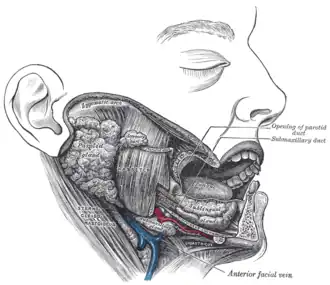

A ce niveau, des microfibres musculaires provenant du muscle buccinateur vont s'étendre sur le conduit parotidien et agir sur l'ouverture de la lumière ductale [4]. Il se termine en s'ouvrant obliquement dans la cavité buccale en regard du collet de la première ou deuxième molaire supérieure.

Le canal s'abouche dans la cavité buccale par un orifice au sommet d'un petit relief de la muqueuse de la joue : la "papille du conduit parotidien". Il se situe donc médialement à la branche descendante de la mandibule.

Schéma anatomique représentant le trajet du canal parotidien- Position des papilles parotidiennes, en regard du collet des deuxièmes molaires supérieures.

- Dissection anatomique représentant le conduit parotidien par rapport au muscle masséter, et à la veine faciale